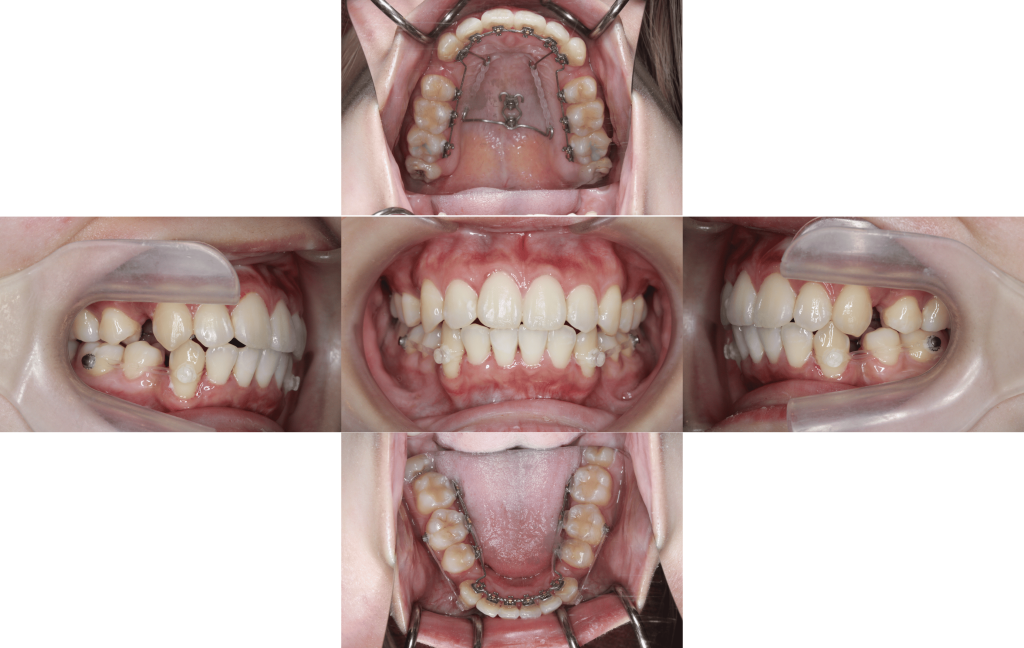

After

約1年10か月後

年齢層

20代

性別

女性

主訴

・前歯が出ている・横顔のシルエットを綺麗にしたい

治療費用

¥1.375.000

治療期間

1年10か月(治療中)

抜歯

上下顎左右第一小臼歯

矯正の装置

裏側矯正(マルチブラケット)

副作用、リスク

歯肉退縮,歯根吸収,疼痛,咬合の違和感,装置の違和感,虫歯,歯肉